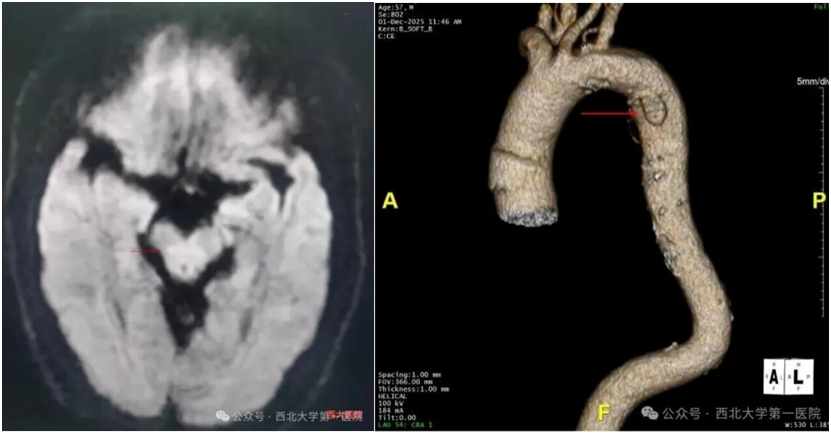

不久前,一位中老年男性突发头晕、说话含糊、一侧肢体无力,被紧急送医。头颅MRI确诊为超急性期延髓脑梗死——延髓掌控呼吸、心跳等核心功能,必须尽快溶栓活血,否则性命堪忧。

但CTA检查又发现,患者还合并了主动脉穿透性溃疡伴壁内血肿:主动脉壁像破了个“溃疡”,周围积血形成了易破裂的“血泡”,死亡率极高。这就形成了治疗死结:治脑梗需用溶栓、抗血小板药“活血”,却会让主动脉血肿更易出血;防出血要止血、控血压,又会让脑梗血栓更难溶解,加重瘫痪甚至危及生命。